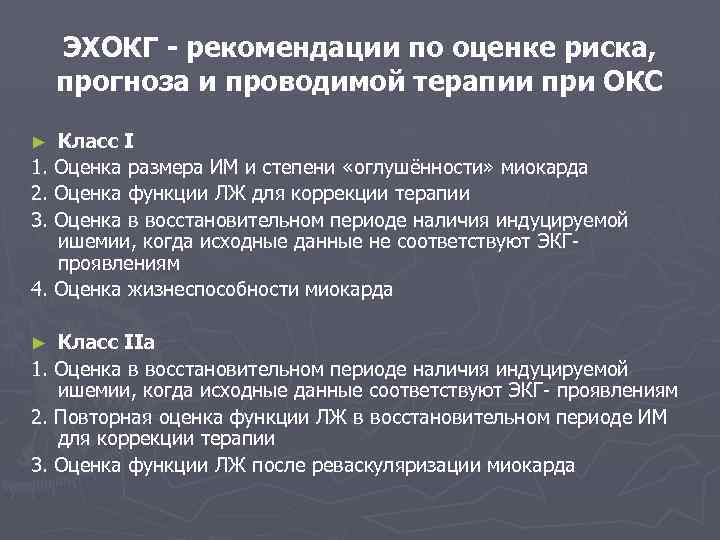

ЭХОКГ - рекомендации по оценке риска, прогноза и проводимой терапии при ОКС Класс I 1. Оценка размера ИМ и степени «оглушённости» миокарда 2. Оценка функции ЛЖ для коррекции терапии 3. Оценка в восстановительном периоде наличия индуцируемой ишемии, когда исходные данные не соответствуют ЭКГпроявлениям 4. Оценка жизнеспособности миокарда ► Класс IIа 1. Оценка в восстановительном периоде наличия индуцируемой ишемии, когда исходные данные соответствуют ЭКГ- проявлениям 2. Повторная оценка функции ЛЖ в восстановительном периоде ИМ для коррекции терапии 3. Оценка функции ЛЖ после реваскуляризации миокарда ►

► Класс IIв Оценка отдаленного прогноза (2 года и более после ИМ) ► Класс III Повторное исследование при отсутствии изменений в клиническом статусе